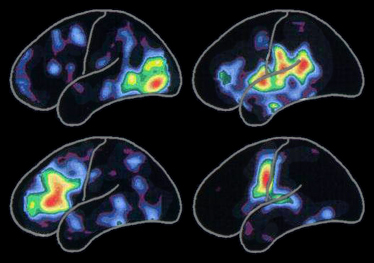

Esta imagem de uma tomografia publicada pela Alzheimer´s Association acima, mostra padrões de atividade cerebral associados com: ler palavras, ouvir palavras, pensar em palavras e dizer palavras, demonstrando claramente que áreas variadas do cérebro estão em funcionamento.

| Imagem Computadorizada de Tomografia por Emissão de Pósitrons |